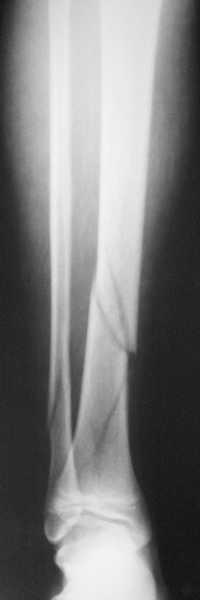

В приложении метафизарный перелом у ребёнка 14лет, с распространением линии перелома на зону роста.

В примере показан не перелом пилона, а эпифизеолиз, м/берцовую кость сознательно не фиксировал(длина её восстановлена, ротации нет),у детей стараемся минимизировать операц.травму, несколько позже разрешил полную нагрузку на ногу(4 недели). Но принцип фиксации б/берцовой кости м.б. таким же.

Проблем с закрытой(прямой или непрямой) репозицией возникнуть не должно, даже при небольшом опыте, перелом как раз для этого, суставная поверхность и метафиз рассколоты, смещение небольшое. В крайнем случае можно сделать неболшой передний доступ для репозиции и остеосинтеза винтами сустава, а дальше обязательно малоинвазивно медиальную плату или аппарат.